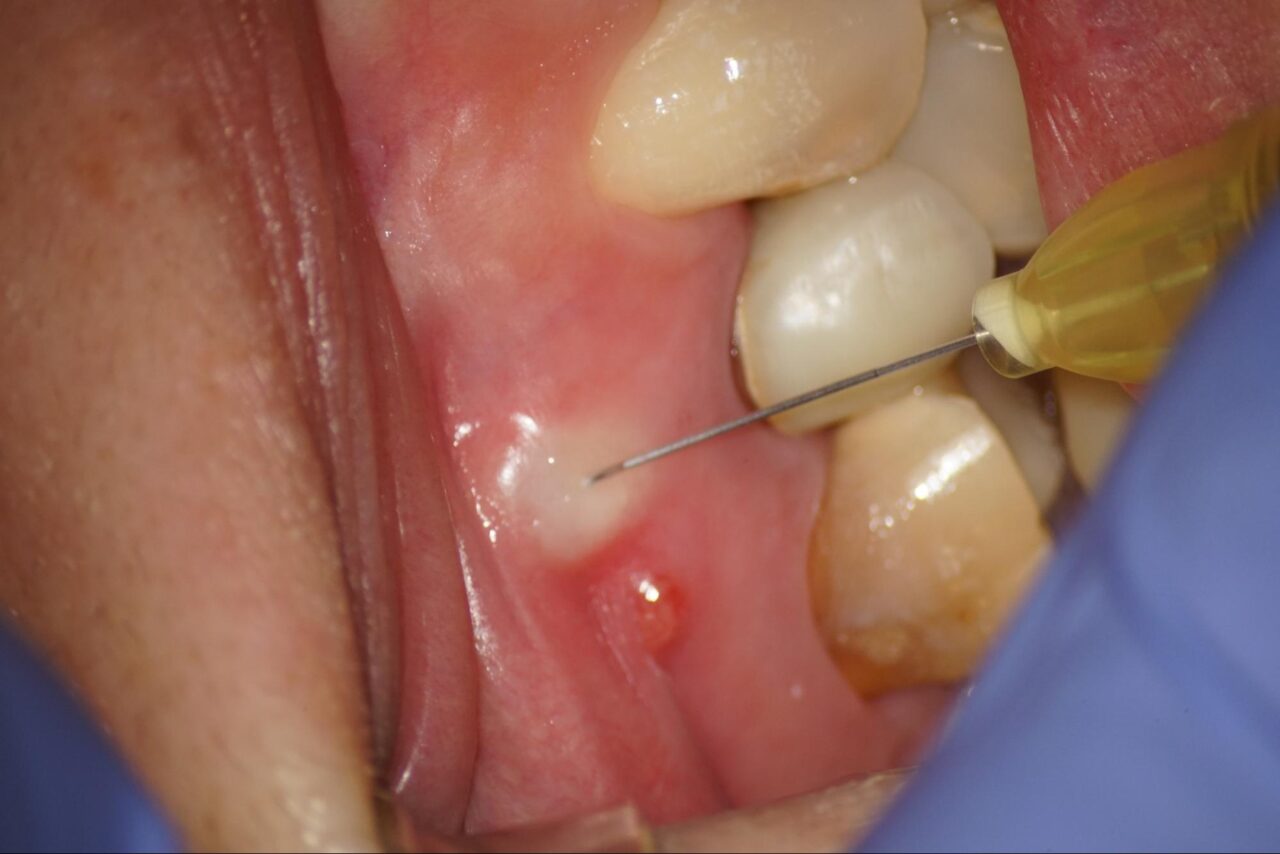

症例2:膿の道、サイナストラクトが存在している歯

膿の道、サイナストラクトが存在している歯では、多くの場合再発、再治療の事が多くあります。

通法通りに先ずは麻酔をします膿の道の部分をさせて、麻酔の針を刺します。これは麻酔薬が膿の道から漏れない様の周辺から麻酔を進めます。